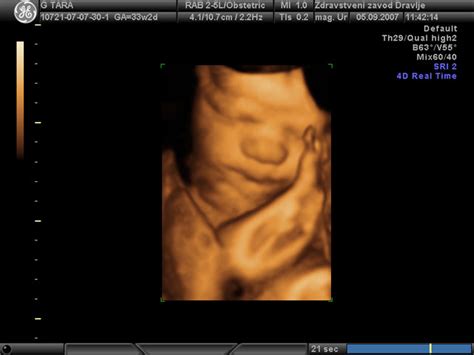

Že med 10. in 14. tednom nosečnosti se opravi ultrazvočna preiskava preko trebuha. Ocenjuje se zgodnji razvoj ploda, tveganje za Downov sindrom in druge kromosomske nepravilnosti. Na željo nosečnice je mogoč tudi prikaz ploda s 3D/4D tehnologijo. V tem času se nosečnici odvzame kri za dvojni hormonski test (DHT). Zanesljivost izvida na osnovi ultrazvočne ocene je približno 80%, skupaj z DHT pa se poveča na okoli 90%.